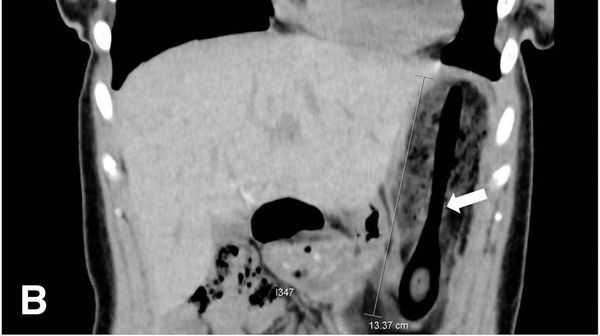

Dokter menemukan sebuah sendok sepanjang 11 cm di dalam tubuh bocah berusia 13 tahun. Sendok itu baru dikeluarkan 10 hari setelah tertelan.